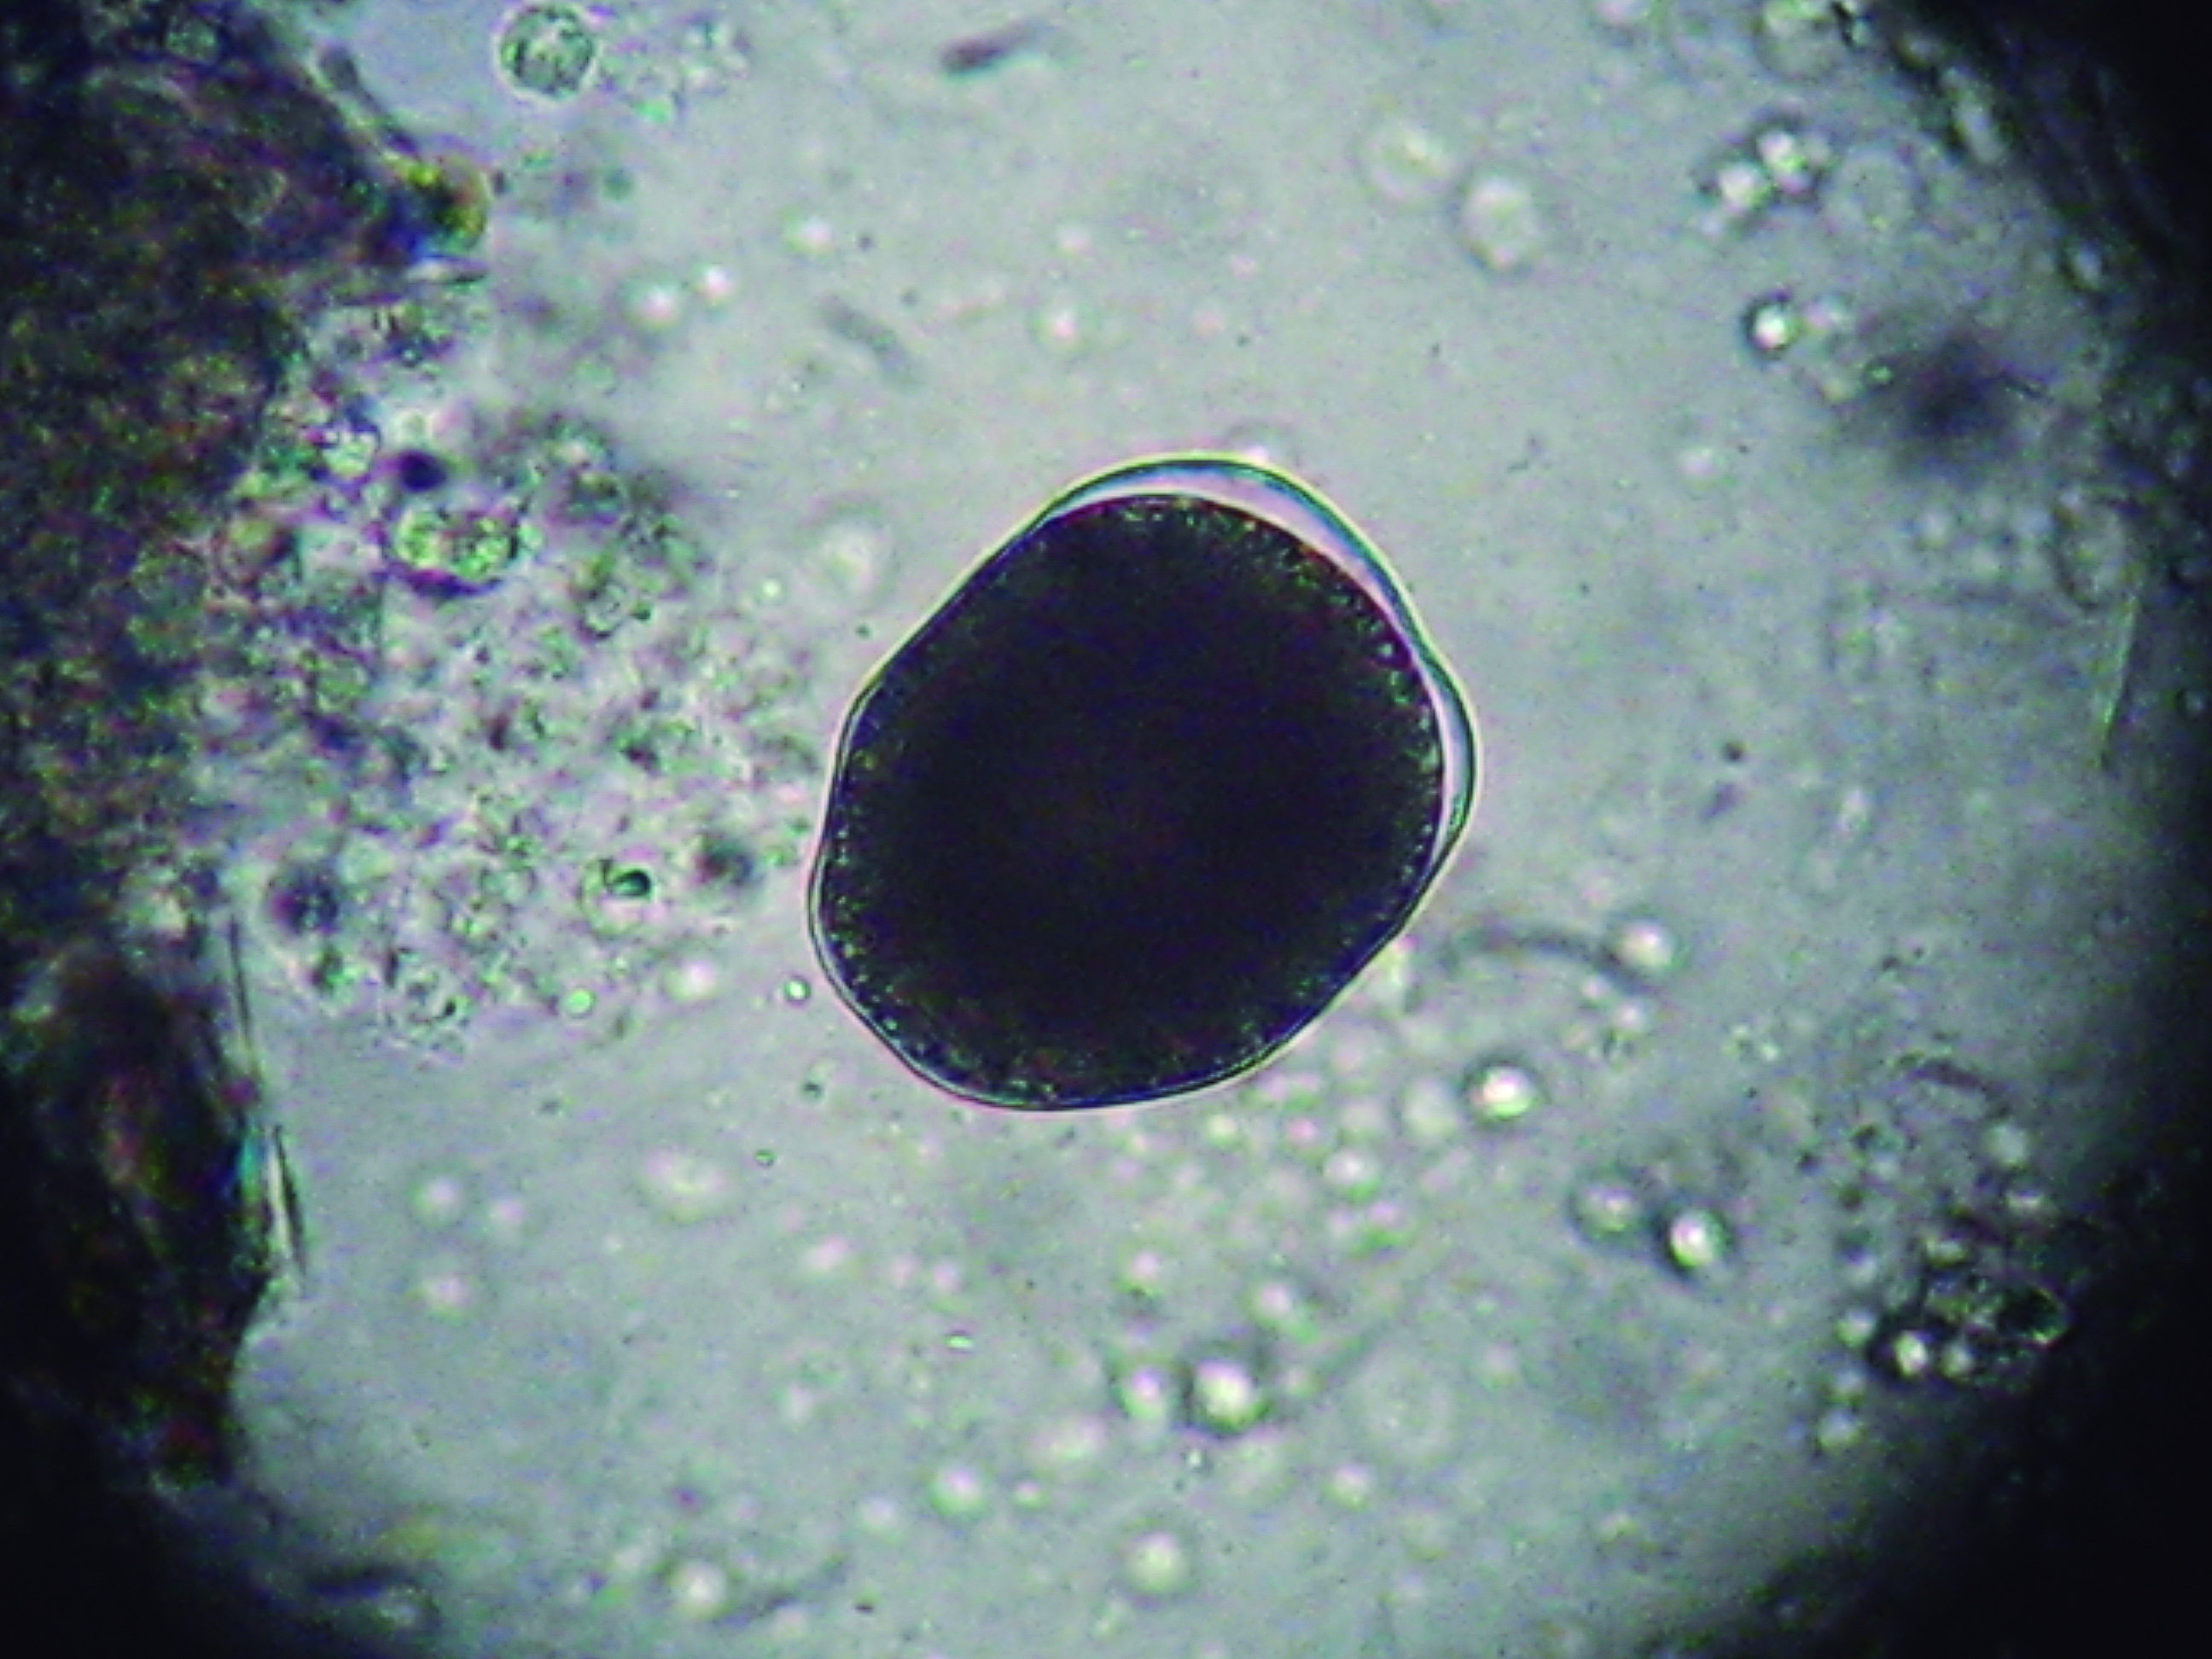

Enteromyxosis

Agent: Enteromyxum leei (Myxidiidae, Myxozoan histozoic parasite).

Symptoms: This Myxosporean parasite infects the intestinal mucosa of gilthead sea bream causing severe weight loss and high mortality. Sea bass may act as a carrier without being affected. Horizontal transmission occurs between fish via pre-sporogonic forms expelled in fecal packets, rather than spores typical of other myxosporeans. Mature spores have a characteristic “croissant” shape with polar capsules at their ends.

Control: No treatment. Prevention involves separating fish of different sizes to reduce transmission, net cleaning and removal of mortalities.